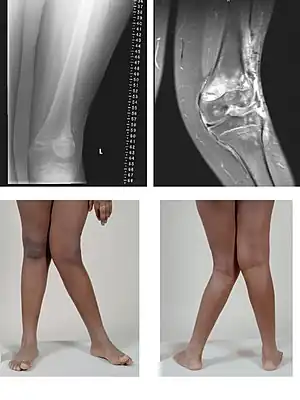

Genu valgum, commonly called "knock-knee", is a condition in which the knees angle in and touch each other when the legs are straightened.[1] Individuals with severe valgus deformities are typically unable to touch their feet together while simultaneously straightening the legs. The term originates from the Latin genu, 'knee', and valgus which means "bent outwards", but is also used to describe the distal portion of the knee joint which bends outwards and thus the proximal portion seems to be bent inwards.

| A very severe case of genu valgum of the left knee following bone cancer treatment | |

Mild genu valgum is diagnosed when a person standing upright with the feet touching also shows the knees touching. It can be seen in children from ages 2 to 5, and is often corrected naturally as children grow. The condition may continue or worsen with age, particularly when it is the result of a disease, such as rickets.[2] Idiopathic genu valgum is a form that is either congenital or has no known cause.